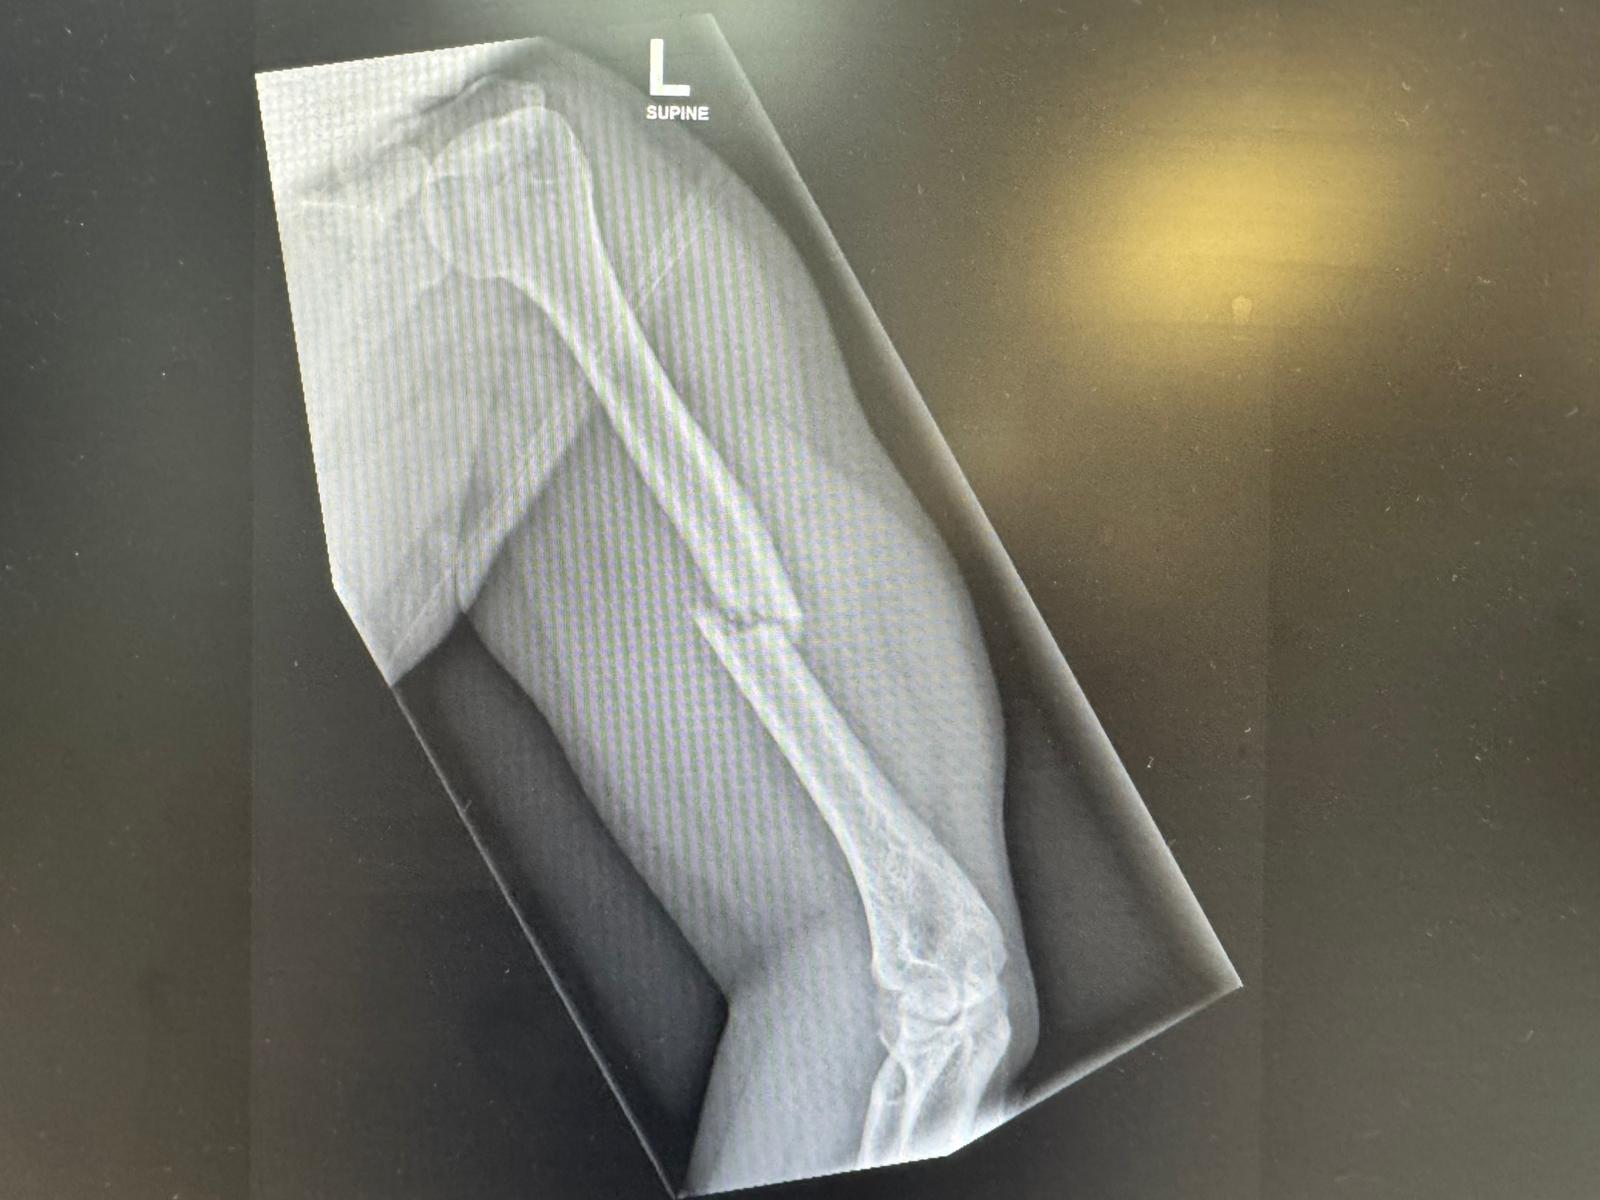

I in hospital for two weeks …. had a bad fall and fracture ……